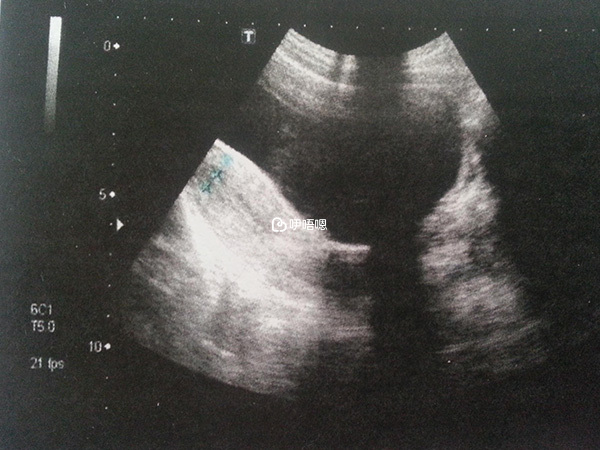

中間還因為我覺得挺好的那位醫生,休產假了,我一直心想著等她回來再去看她,只因她跟我講說,很多人促排一次就懷上了。後來一直到15年年底我才開始深圳北大醫院看,到時B超才寫明我說是,雙側卵巢多囊性改變。

到了兩週後的B超,當時心裡感覺到有隱隱的不安,結果檢查發現胎停了。開始我心想,肯定是自己感性的煩惱,做B超的護士,一把探頭放入陰道,就停了下來,還發出了,“嘖”的聲音。

直到一會,她問我,上次查的結果怎麼樣,我說有胎心胎芽啦,她說,自上次之後沒有長。我聽了心裡一咯噔,什麼叫沒長?她說,沒有心跳了,估計已經掛了。